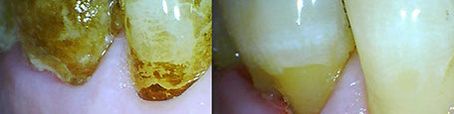

• Carillas

Las carillas dentales son pequeñas láminas que se pegan en la cara externa de los dientes mediante un cemento con el fin de mejorar la imagen dejando a la vista una sonrisa mucho más atractiva. Es un tratamiento principalmente estético que permite construir la dentadura que el paciente desea, ya sea por necesidad (traumatismos, cambios de coloración, desviaciones) o por el simple hecho de querer lucir una sonrisa más bonita.